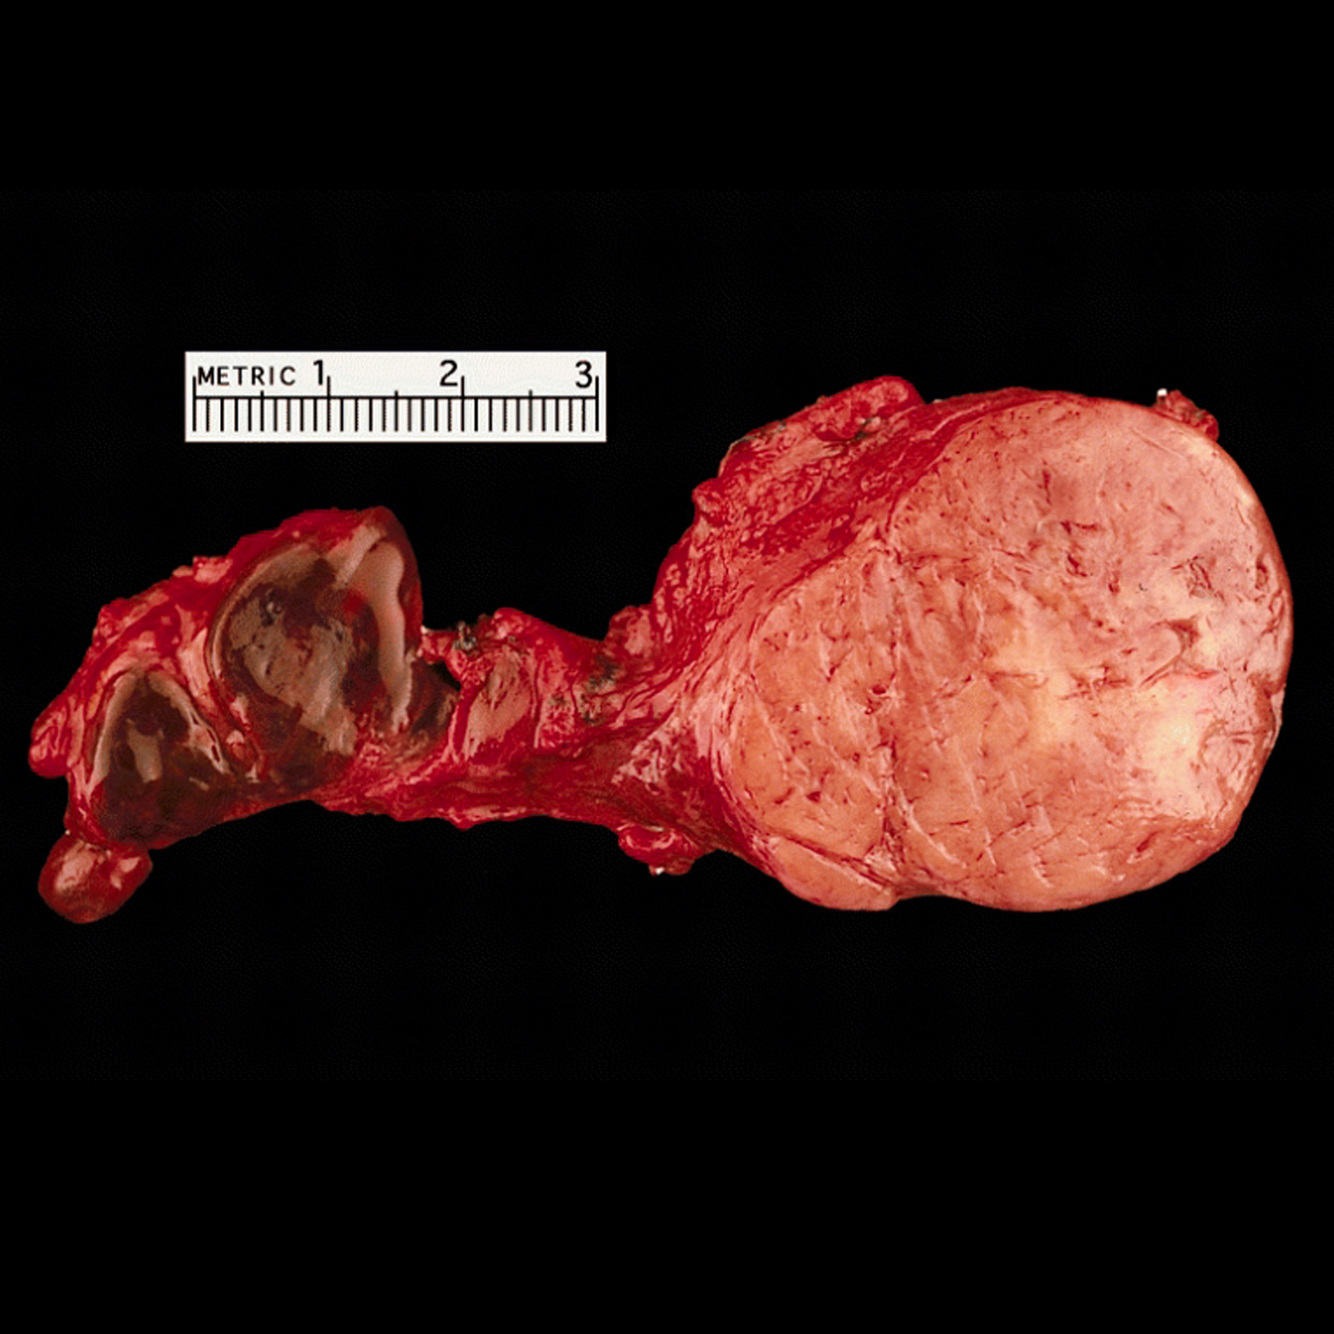

Q

weight loss

Gallbladder carcinoma is uncommon, with a poor prognosis. Five year survival is less than 5%.

It may present insidiously with weight loss or a palpable mass or with jaundice.

Case Discussion

Large distended gallbladder, which is entirely occupied by a solid internal mass, with internal haemorrhage.

Histopathology confirmed the radiological suspicion of a gallbladder carcinoma